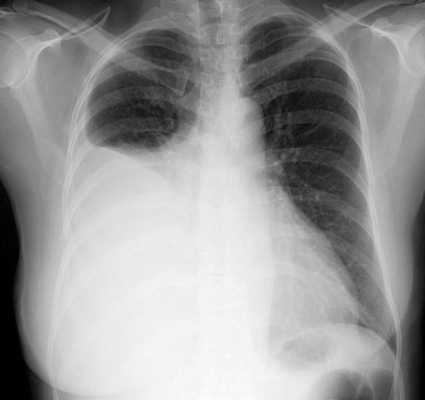

плевральный выпот на рентгеновском снимке

Перечисленные причины обычно приводят к диагностической торакоскопии, тогда как необходимость рассечения рубцовых сращений, удаления воздуха или иного содержимого, иссечение кист или опухолей — показания к лечебной торакоскопической операции.